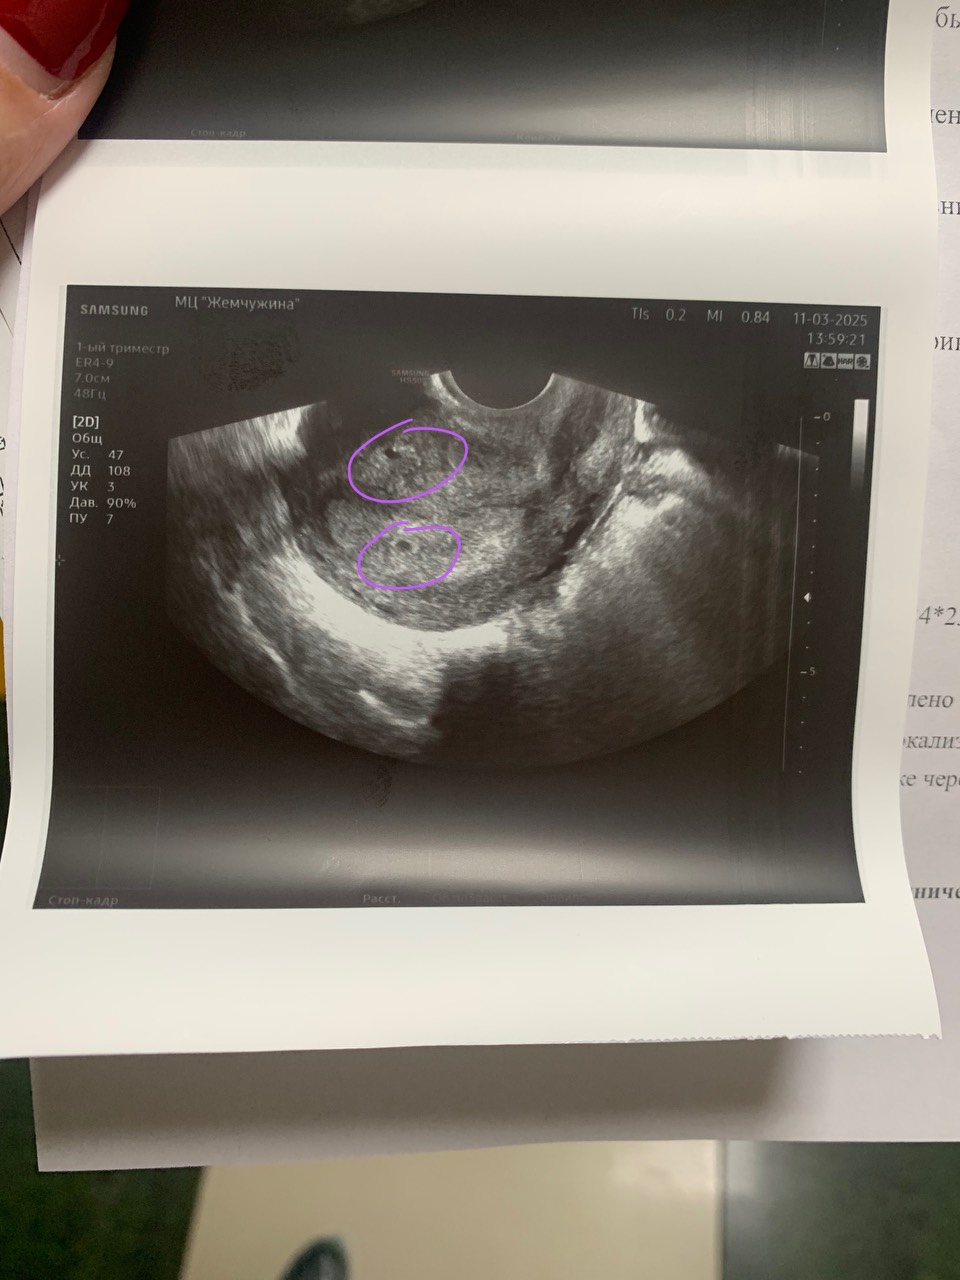

4.03 хгч был 26, 11.03 хгч 815,на узи сказали что в матке визуализируется плодное яйцо как- бы,но точно сказать не могут,назначили прием через неделю,подскажите пожалуйста,у кого было такое,либо беременность двойней,как у вас было?

Вот здесь эндометрий и похоже на плодное яйцо,а выше это непонятно что,но точно не пя,плодное яйцо крепится в функциониональный слой эндометрия и на фото у вас вот он

У вас двурогая матка? На фото похоже на 2 эндометрия с 2мя плодными яйцами 😁